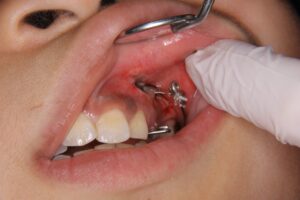

● 牽引治療の流れ

-

口腔外科で歯ぐきを切開し、埋伏歯の一部を露出させる

露出した埋伏歯に小さな装置(ボタン)を付ける

矯正装置のワイヤーとゴムの力でゆっくり口腔内へ引き出す